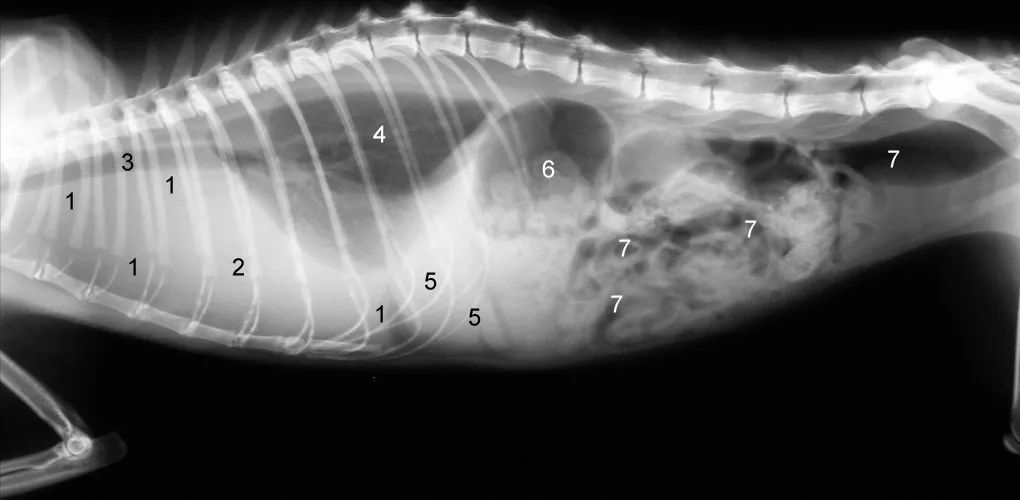

猫传腹猫咪的X光片:1因胸腔下部积液导致弥漫性阴影,2心脏因胸腔积液而无边界可见3气管4肺,5肝脏, 6胃, 7肠

这只猫的胸部有大量液体,因此很难识别正常器官。肺部无法完全扩张,导致呼吸困难,需要立即抽取腹水。